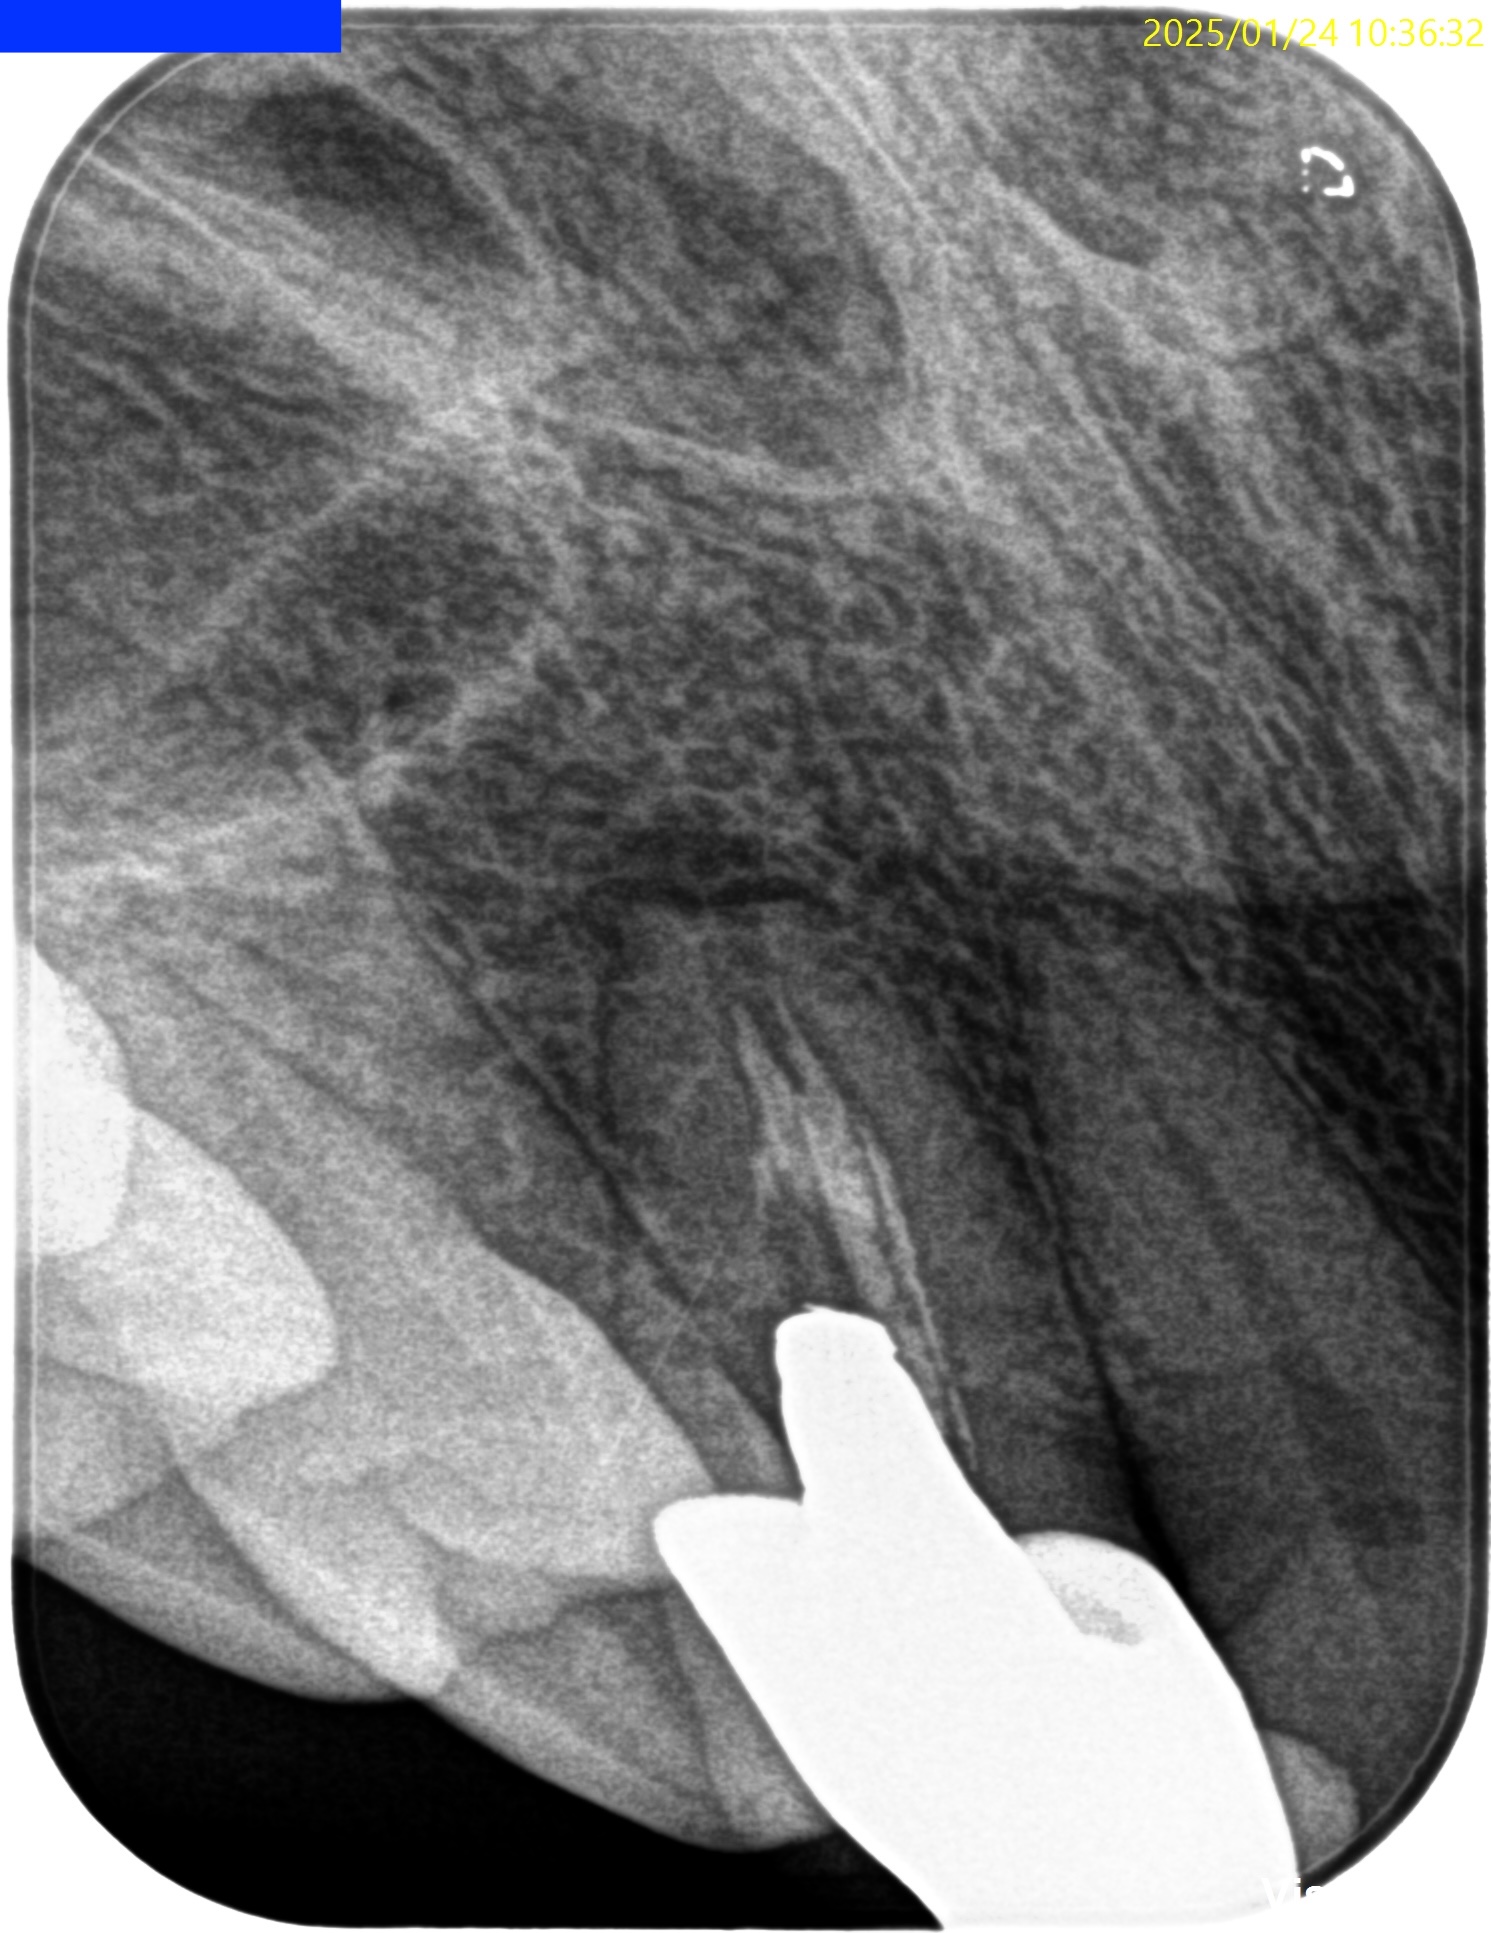

Pre-op Endo test(2025.1.24)

根尖が既に開いており、圧痛があったことから治療は再根管治療ではなく、歯根端切除術であるということがわかる。

クラウンのマージンより11.5mm下方に#7のApexはあり、そこを3mm切断するには頬舌的に4.4mmの幅があるということがわかる。

Pulp Dx: Previously treated

Periapical Dx: Asymptomatic apical periodontitis

Recommended Tx: Core build up w Fiber Post⇨Apicoectomy